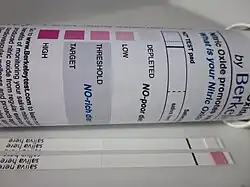

Cardio-protective nitric oxide is generated in the body by a family of specific enzymes, nitric oxide synthase. An alternative pathway for the generation of nitric oxide is the nitrate-nitrite-nitric oxide pathway in which dietary inorganic nitrate is sequentially reduced to nitric oxide.[70] A necessary and obligatory step in the generation of nitric oxide by the non-nitric oxide synthase or alternative pathway involves the uptake of nitrate by the salivary gland, excretion in saliva, and subsequent reduction to nitrite by oral commensal bacteria in the mouth.[71]

Salivary nitrite is then further chemically reduced in blood and tissue to nitric oxide resulting in the lowering of blood pressure, inhibition of platelet aggregation, increasing cerebral blood flow and flow-mediated dilation, and decreasing oxygen cost during exercise.[72][73][74] A principal source of dietary inorganic nitrate, which is reduced to nitric oxide in the body, is from leafy green vegetables.[75][76] The blood pressure lowering effects of leafy green vegetables, in particular, spinach and arugula, are abundant in anti-hypertensive diets such as the DASH diet.[77] Several papers have shown saliva nitrite levels correlate with blood nitrite levels which both serve as meaningful surrogates for blood pressure lowering effects.

Sobko et al. shows that Japanese traditional diets rich in leafy vegetables elevated both plasma and saliva nitrite levels with a corresponding decrease in blood pressure.[78]

Webb et al. in 2008 reinforced the obligatory role of saliva in humans to generate nitric oxide. Here, they showed ingestion of beet juice, a nitrate-rich food, by healthy volunteers markedly reduced blood pressure and by disrupting saliva, either by spitting or interrupting the bioconversion of dietary nitrate to nitrite in the mouth with anti-bacterial mouthwash, the chemical reduction of nitrate to nitrite to nitric oxide with an associated decease in blood pressure was abated. By blocking saliva from recirculating or preventing salivary nitrate from being chemically reduced to nitrite, it prevented a rise in plasma nitrite levels, and blocked a decrease in blood pressure as well as abolished nitric oxide-mediated inhibition of platelets aggregation confirming the cardio-protective effects were attributable to nitric oxide via the conversion of nitrate to nitrite in saliva.[79]

In a series of reports by Ahluwalia and colleagues, they showed in a cross over protocol of 14 volunteers who ingested inorganic nitrates, plasma and saliva nitrite level increased 3 hours post ingestion with a significant reduction of blood pressure. Nitrate extracted from blood by the salivary gland, accumulates in saliva, which is then reduced to nitric oxide to have a direct blood pressure lowering effect. Decreasing saliva nitrite in volunteers that already had elevated levels, a rise in systolic and diastolic blood pressure resulted. Furthermore, pre-hypertensives may be more sensitive to the blood pressure lowering effects of the dietary nitrate-nitrite-nitric oxide pathway.[80][81][82] Monitoring the bioconversion of plant-derived nitrate into salivary nitrite serves as a surrogate biomarker for total body nitric oxide status.[77]